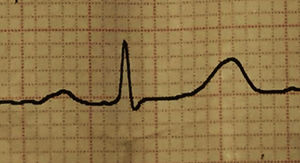

Acude al consultorio de medicina interna para evaluación prequirúrgica por una cirugía menor (extracción de lipoma), y un familiar refiere que una semana después de inicio del tratamiento con olanzapina el paciente presenta tendencia al sueño, además de manifestar mareos y cansancio. Al examen físico destaca una presión arterial de 70/40mmHg, frecuencia cardiaca de 44latidos por minuto, y en el examen neurológico una escala de coma de Glasgow de 14 puntos. El paciente se encontraba somnoliento, y en el electrocardiograma se evidenció bradicardia sinusal con bloqueo cardiaco de primer grado (figs. 1 y 2).

Otros efectos reportados a nivel cardiovascular son la bradicardia, el bloqueo cardiaco de diferentes grados, la hipotensión arterial e hipotensión ortostática4, incluso cuadros de embolismo pulmonar masivo5 y cardiomiopatía dilatada6.

En el caso presentado el efecto de la olanzapina preferentemente fue cardiovascular, presentando hipotensión y bloqueo cardiaco, y se llegó a la conclusión de que la olanzapina era la causante del cuadro por 3 motivos: la sintomatología empezó cuando el paciente inició el tratamiento con olanzapina, se buscó otra causa asociada no encontrándola y los síntomas desaparecieron y el electrocardiograma se normalizó tras suspender el medicamento.